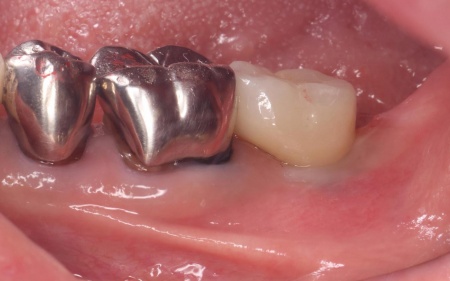

拝見したところ、左下の一番奥の歯(第2大臼歯)の歯茎に腫れが認められました。

レントゲン撮影を行って詳しく調べたところ、歯根が縦方向に割れている「歯根破折」が疑われる状態です。

歯根破折は、過去に神経の治療を行った歯に起こりやすいトラブルで、今回のケースでは被せ物の下で破折が進行していたと考えられます。

まずは左下奥歯に装着されていた被せ物を慎重に除去し、歯根の状態を直接確認します。

その結果、歯根破折が明確に認められたため、歯の温存は困難であると判断しました。

歯根破折が疑われました。